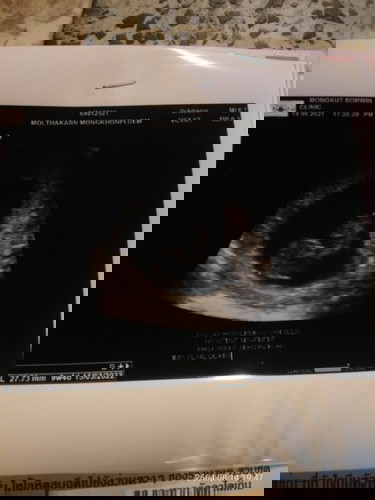

ท้อง9วีคหมอนัดซาวดูอายุครรภ์เจอตัวเด็กแต่ไม่เจอหัวใจเด็ก...จะเจอหัวใจเด็กช้าสุดกี่วีคคะแร้วถ้าเดกไม่มีหัวใจเดกจะหยุดการเจริญเติบโตมั๊ยคะ..#ไม่มีอาการผิดปกติ #คุณหมอจะหั้ยเอาออกอย่างเดียวเรย😭😭

อันนี้ไม่เหนหัวใจเรยค่ะแม่